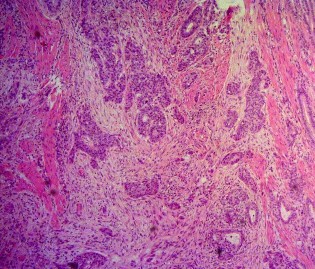

Ảnh 5. Bệnh phẩm khối tá tụy | Ảnh 6. Tế bào học: UTBMT ống tụy. Mã số SR0125, nhuộm H&Ex50 |

Ảnh 7. Tế bào học: UTBMT ống tụy. Mã số SR0125, nhuộm H&E x 100 | Ảnh 8. Tế bào học: UTBMT ống tụy. Mã số SR0125, nhuộm H&E x 100 |